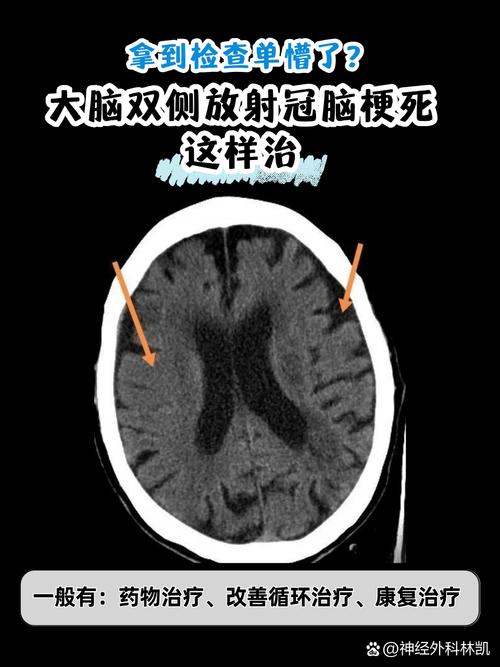

非常理解您此刻的担忧和焦虑,当CT报告显示“脑梗”时,这确实是一个需要严肃对待的信号,请不要慌张,现代医学对于脑梗已经有了一套成熟、有效的应对方案。

以下是发现脑梗后,您需要了解和遵循的核心步骤和注意事项,请务必仔细阅读。